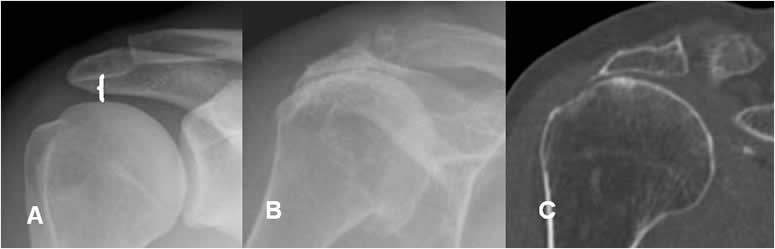

Fig 44. Luxación posterior.

A: Rx AP. Espacio glenohumeral normal.

B: Rx AP. Aumento del espacio glenohumeral, por luxación posterior.

Espacio acromiohumeral:

Es la distancia vertical entre el borde inferior del acromión y el superior de la cabeza del húmero. El valor normal oscila entre 6 y 14 mm y disminuye en los casos crónicos, de ruptura del manguito rotador. (1, 11). (Fig 45).

Fig 45. Ruptura del supraespinoso.

A: Rx AP. Espacio acromiohumeral normal.

B: Rx AP y C: TAC reconstrucción coronal. Cambios degenerativos con pérdida del espacio acromiohumeral y esclerosis asociada, por ruptura crónica del supraespinoso.